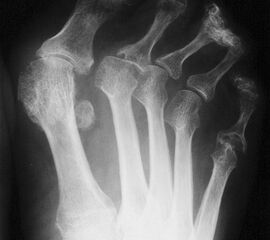

Dorsoplantare Darstellung des Vorfußes. Fortgeschrittene Destruktion des Metatarsophalangealgelenks am 5. Strahl und Lateraldeviation der Zehen.

Abbildung 4